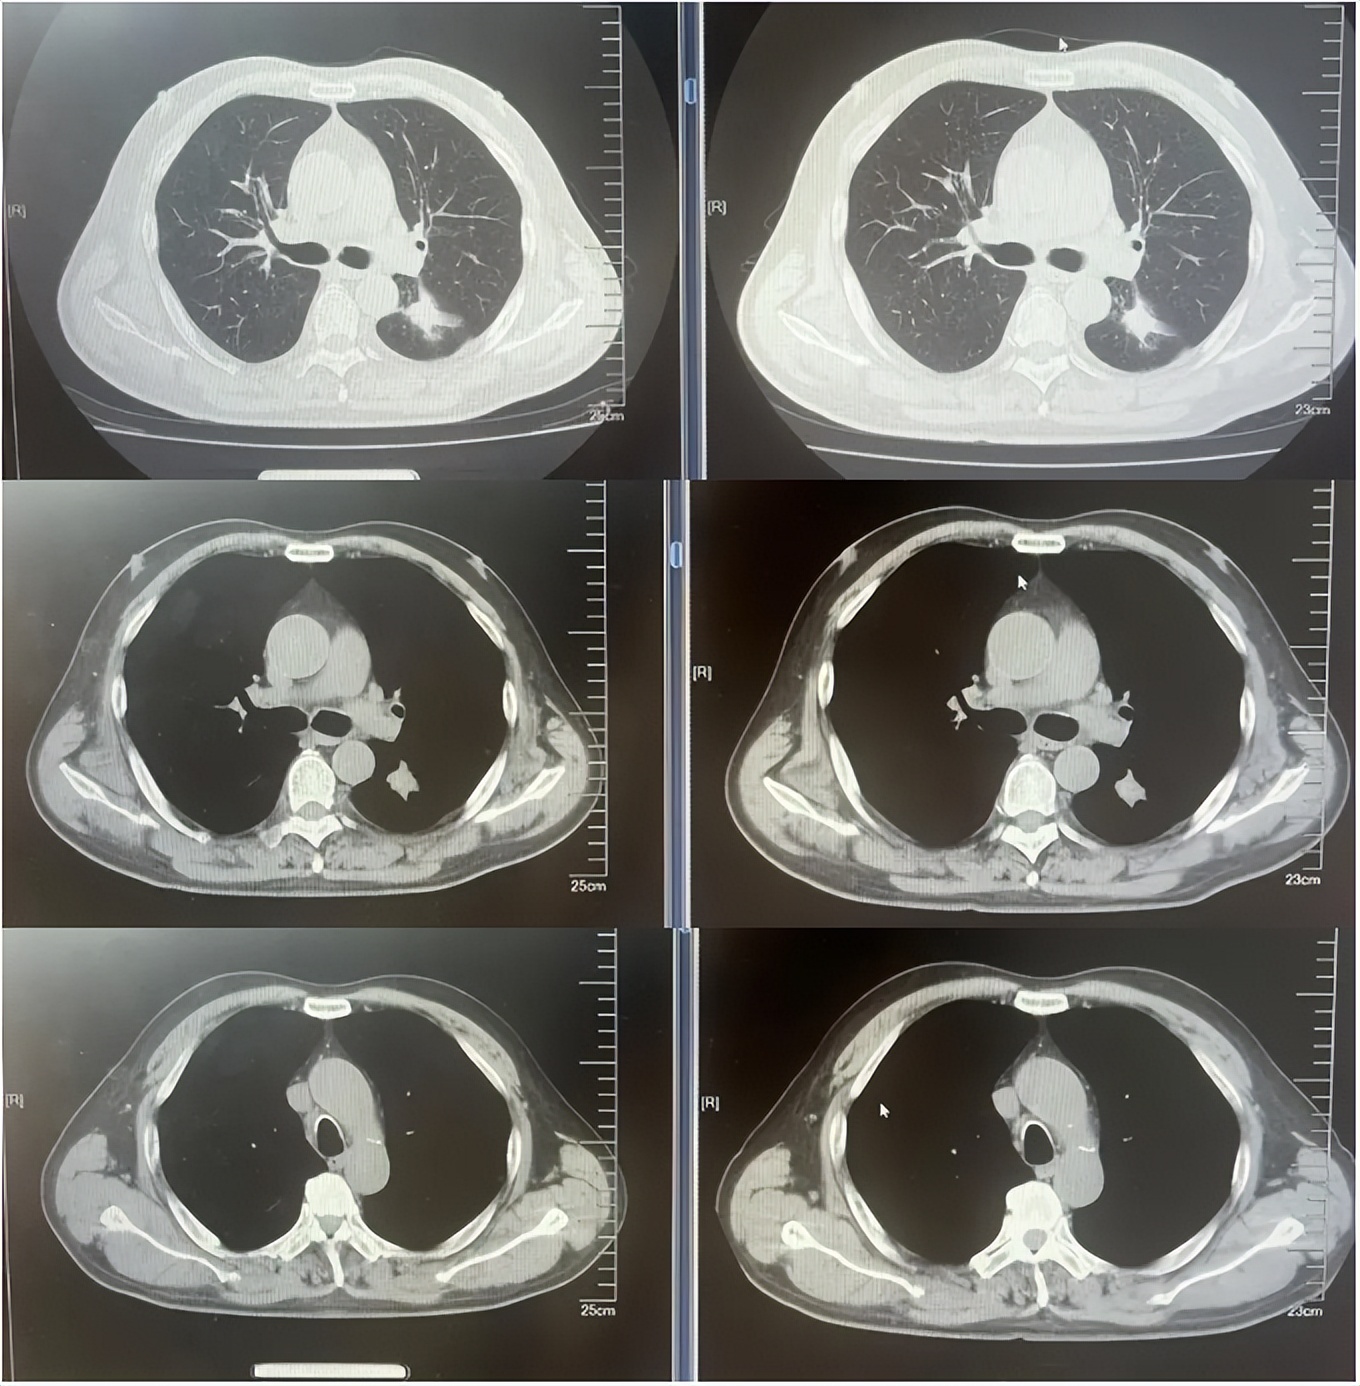

病例1:患者男,68岁。2024年6月以“胸闷气短1个月”为主诉于当地医院检查治疗。查CT提示左肺下叶肿物,纵隔、双肺门多发肿大淋巴结,左侧胸腔积液,左侧胸膜增厚。于当地医院行胸水穿刺引流查癌细胞提示肺腺癌。临床分期:cT2aN3M1a IVA期。患者于当地医院行血液基因检测未见敏感突变,使用AP方案化疗后病情进展。2025-1入我院后行肺穿刺活检,病例提示腺癌。行基因检测提示:ERBB2突变(丰度3.5%)。行德曲妥珠单抗(T-DXd)治疗至今。最佳疗效PR,目前持续有效中,PFS已超过7个月。患者使用德曲妥珠单抗期间出现II级恶心呕吐,经对症治疗可缓解。

德曲妥珠单抗治疗4周期(2025.5)疗效对比

德曲妥珠单抗治疗6周期(2025.7)疗效对比